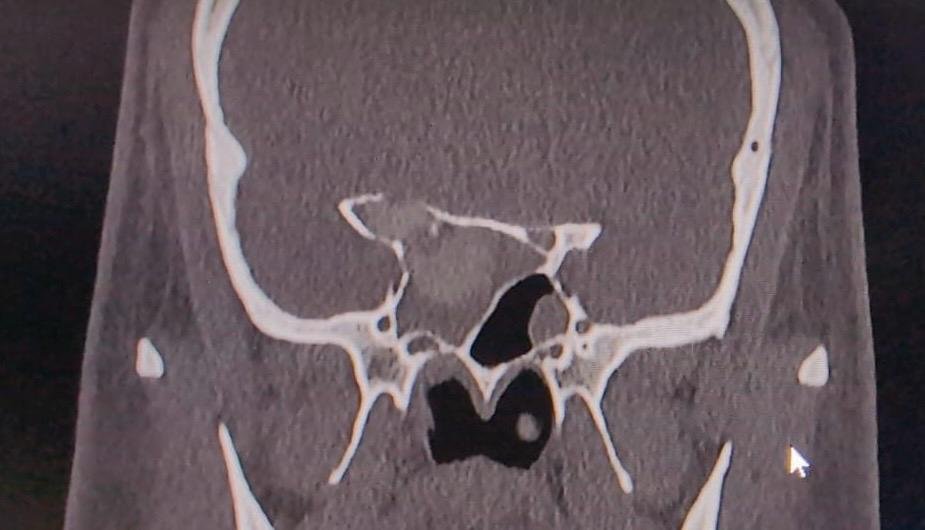

A CT scan of Dr. RG’s sinuses revealed a concerning diagnosis: nasal polyposis and fungal sinusitis. These conditions are serious because they can lead to the compression of the optic nerve inside the sphenoid sinus, which is responsible for vision. This compression is rare but, if not treated promptly, could result in permanent blindness in the affected eye.

During the surgery, the medical team discovered that the fungus had spread throughout all the sinuses and even reached the space between the optic nerve and the brain’s protective layer in the sphenoid sinus. The surgeons carefully removed all the fungal tissue and successfully decompressed the optic nerve, freeing it from the swollen tissue surrounding it.

Dr. Varun Rai, the ENT consultant, Sir Gangaram Hospital, who led the surgery, explained, “These types of surgeries are extremely specialised due to the fact that the optic nerve is very delicate and a slightest misstep can lead to permanent blindness.” Special instruments were used around the nerve to ensure that no additional pressure was applied while achieving complete clearance of the fungal tissue. The surgery was meticulous, and the optic nerve was decompressed by 270 degrees, leaving the blood supply to the nerve intact.

Sir Ganga Ram Hospital (SGRH) has been pioneering advanced ENT surgeries. The hospital recently acquired the Image Guided Navigation system, allowing surgeons to use real-time surgical mapping based on preoperative CT scans. This technology ensures complete disease clearance with minimal complications. SGRH was the first private hospital in Delhi to start this program and continues to lead in training and education across the country.